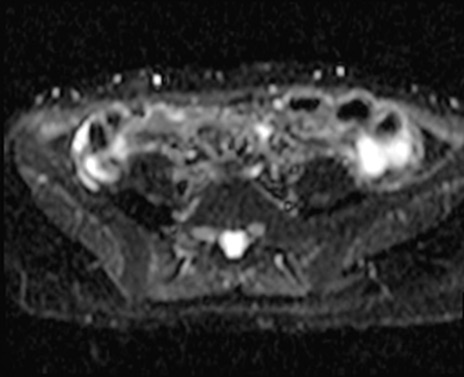

MRI(4日後)